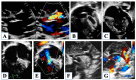

Hypoplastic left heart syndrome is a spectrum of complex congenital cardiac defects. Although in borderline cases, biventricular repair is a viable option, in the majority of cases, univentricular palliation is the treatment of choice. Hybrid palliation can be a valid alternative to classic Norwood operation in the neonatal period, especially in selected cases such as high-risk patients or borderline left ventricles. Echocardiography is the main diagnostic modality in this pediatric population, from the fetal diagnosis to the subsequent surgical steps of palliative treatment. Hybrid palliation is performed after birth and is characterized by surgical banding of the pulmonary arteries along with transcatheter stenting of the ductus arteriosus. There are some peculiar aspects of cardiac imaging that characterize this type of palliation, and that should be considered in the different phases before and after the procedure. We aimed to review the current literature about the role of echocardiography in the management of patients with hypoplastic left heart undergoing hybrid palliation.